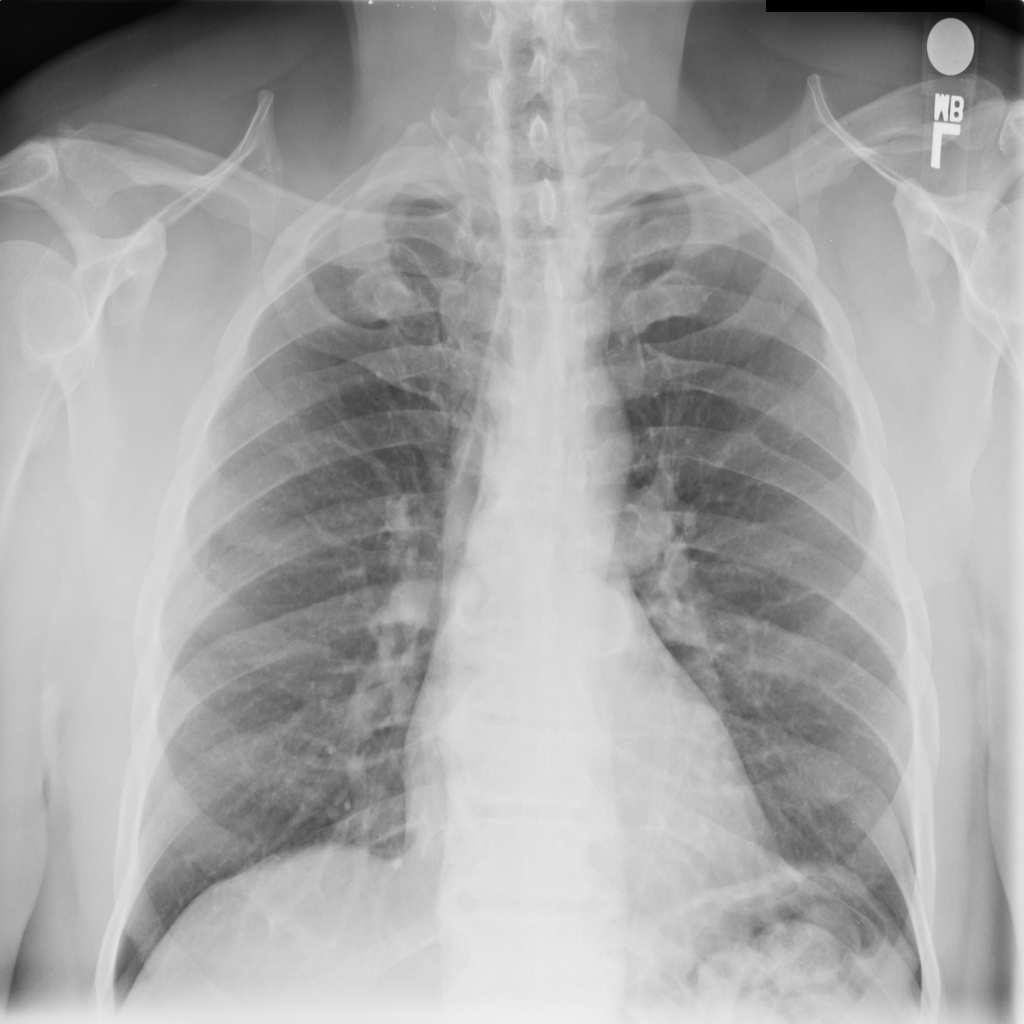

Mass

A mass is a larger focal opacity or lesion seen on the image. It is a descriptive finding that can have several causes and usually needs more imaging or clinical context to characterize.

PAT-50E5 · IMG-008Mass

PAT-50E5 · IMG-008

PA